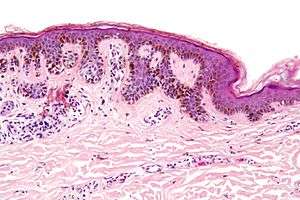

| Micrograph of a dysplastic nevus showing the characteristic rete ridge bridging, shouldering, and lamellar fibrosis. H&E stain. | |

Low magnification

Intermediate magnification

Very high magnification